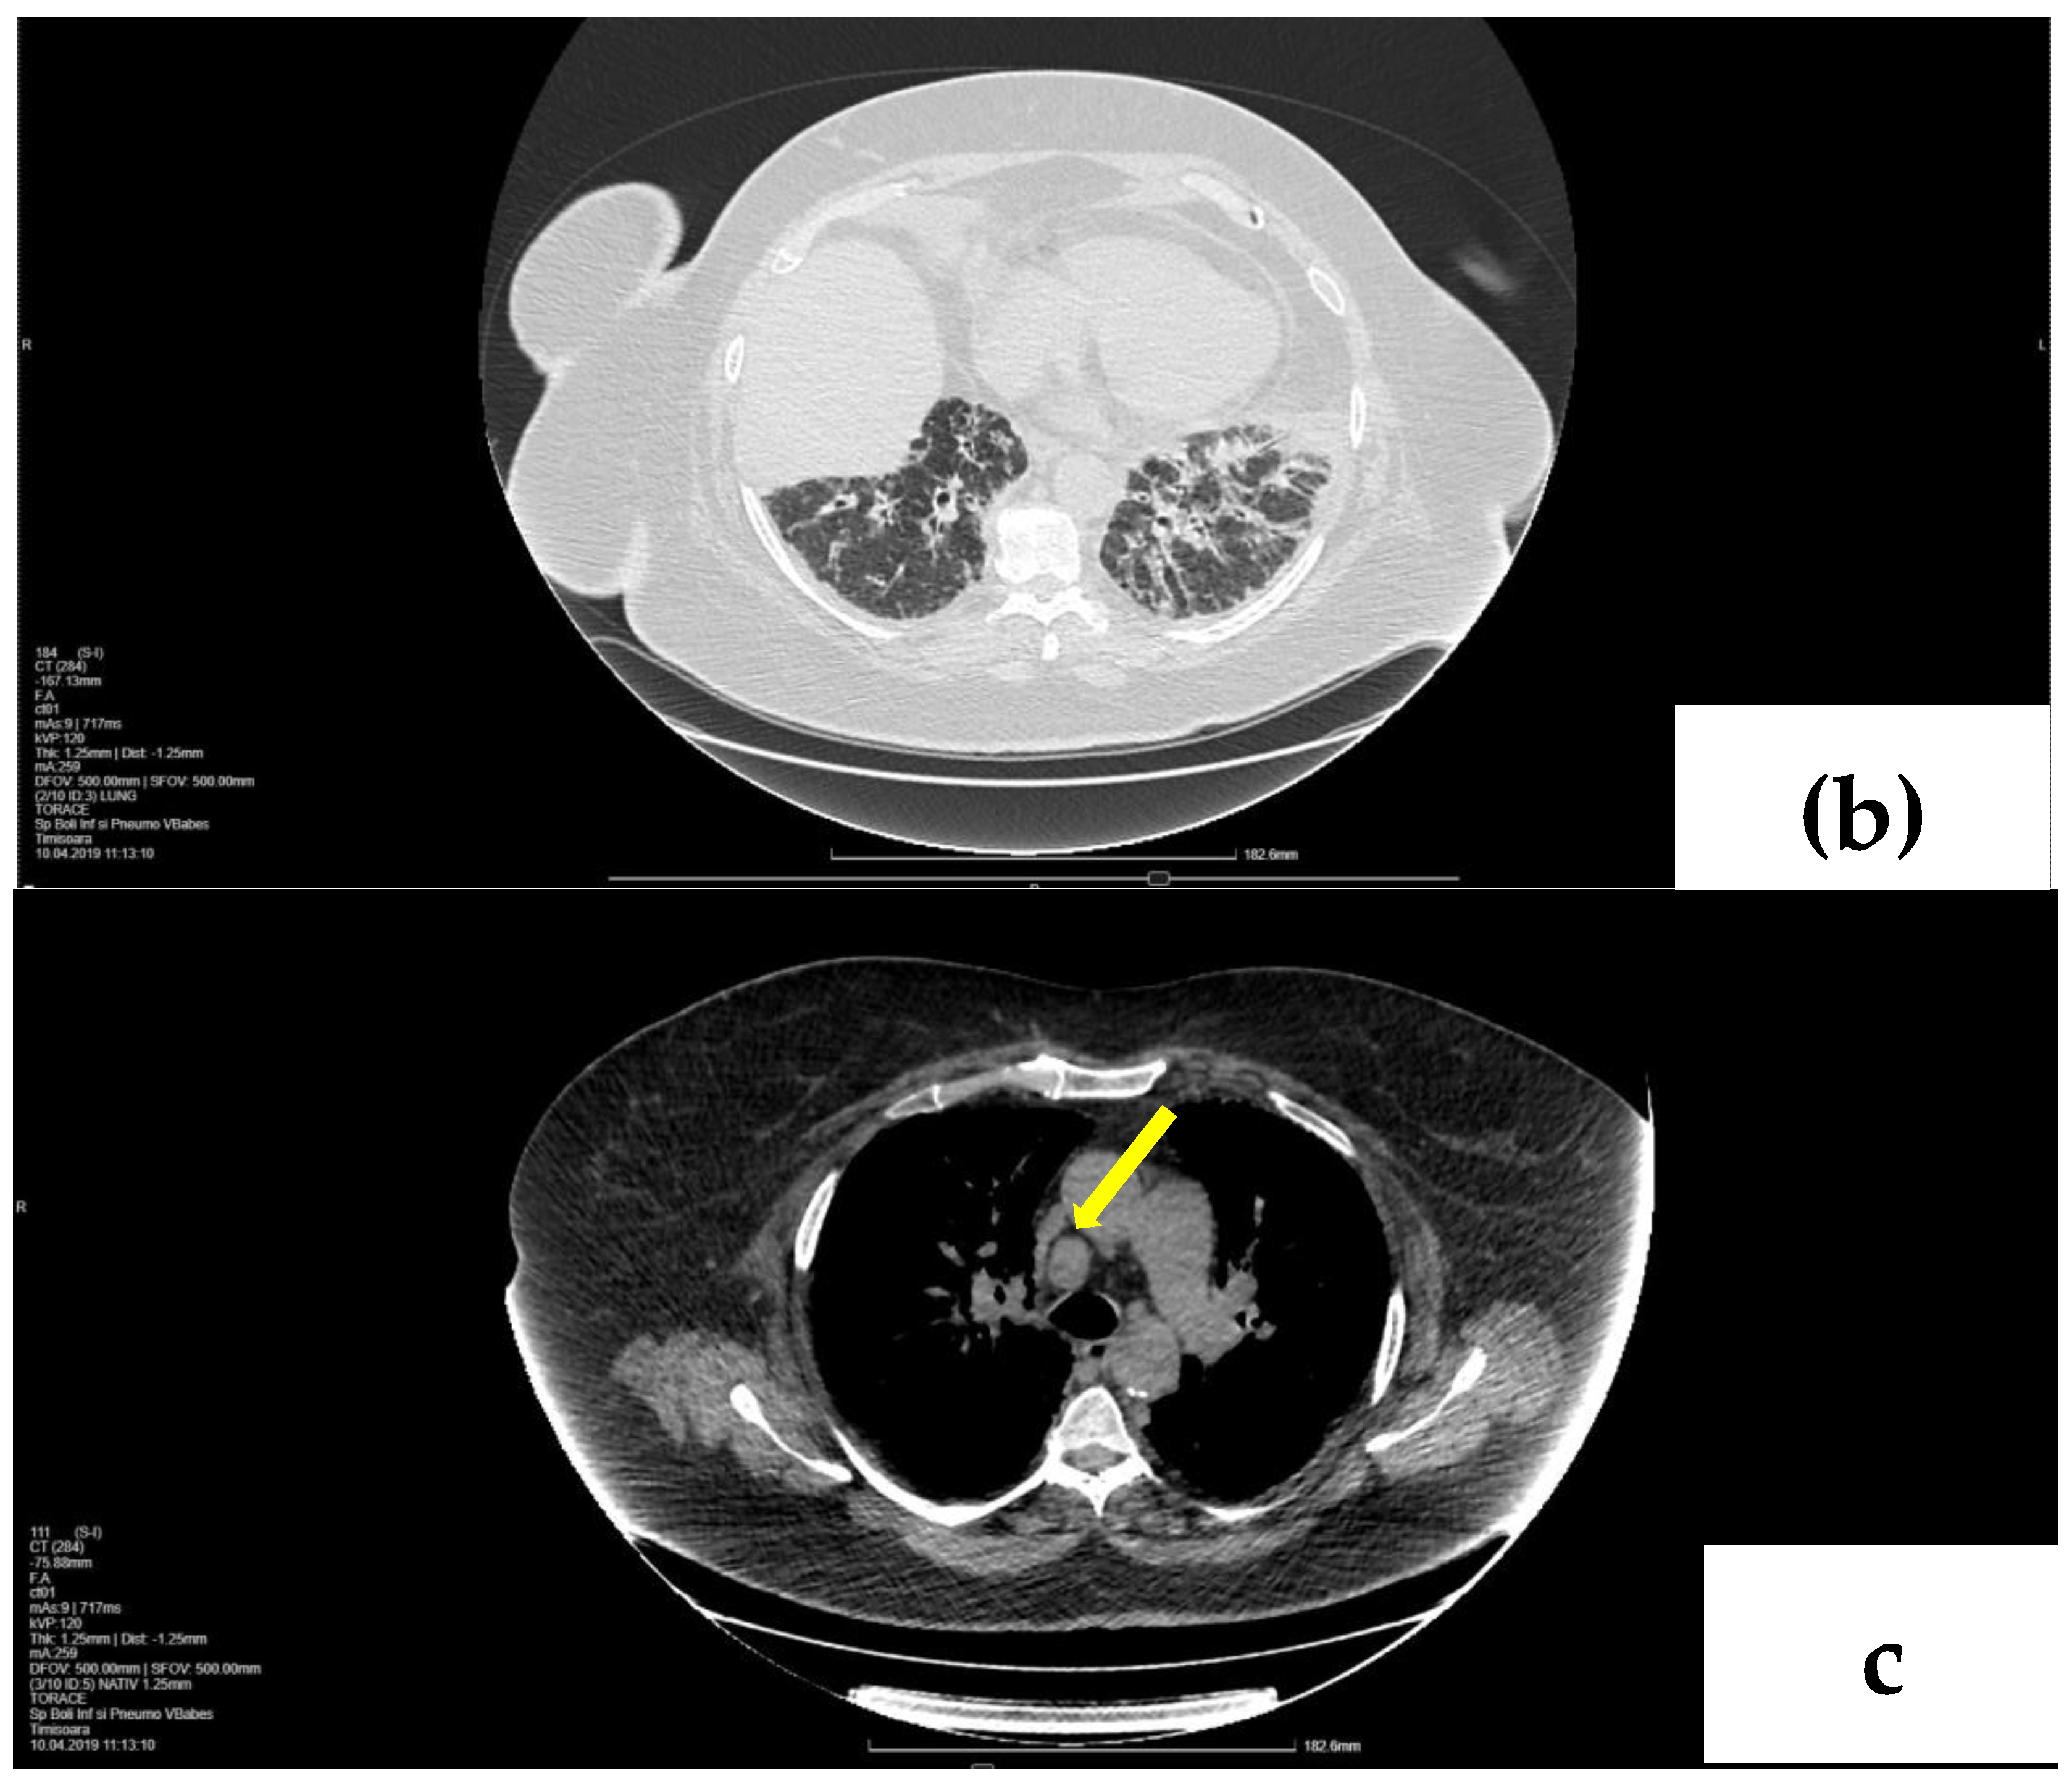

2. Case Presentation

2.1. Laboratory, Radiological, and Histological Examinations